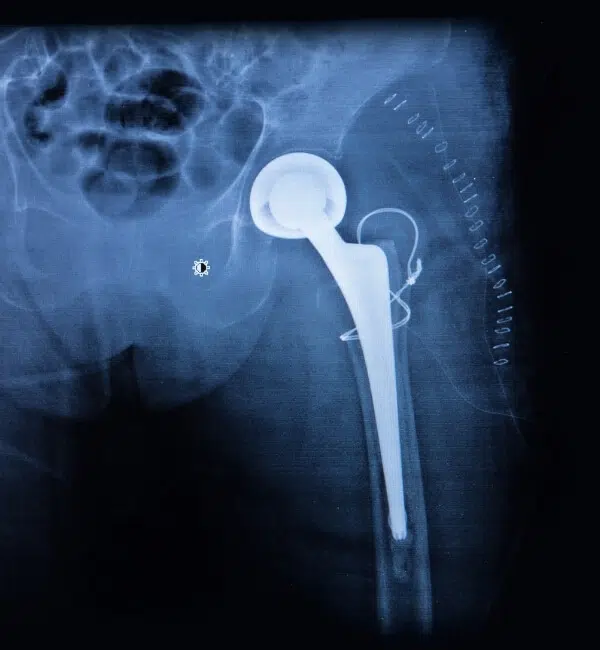

Endoprotezy biodrowe stanowią przełomowy krok w nowoczesnej ortopedii, szczególnie w leczeniu zaawansowanych zwyrodnień stawów biodrowych i kolanowych, które mogą skutecznie utrudniać codzienne funkcjonowanie pacjentów, ograniczając ich mobilność oraz wpływając na jakość życia.

Zabieg endoprotezoplastyki biodra pozwala nie tylko na skuteczne wyeliminowanie przewlekłego, uporczywego bólu, ale także na pełne przywrócenie sprawności ruchowej, oferując pacjentom komfort oraz wieloletnią trwałość efektów operacyjnych. Dzięki odpowiednio dobranym protezom możliwe jest przywrócenie naturalnej biomechaniki stawu, co znacząco wpływa na wygodę i płynność ruchów.

Zabieg endoprotezoplastyki biodra jest skrupulatnie zaplanowany i opiera się na najnowszych osiągnięciach technologicznych, takich jak wykorzystanie trwałych i wysoce biokompatybilnych materiałów. Dzięki nim protezy są odporne na ścieranie, co pozwala pacjentom cieszyć się pełną swobodą ruchów przez wiele lat po operacji. Endoprotezoplastyka to szansa na nową jakość życia dla osób, które przez długi czas zmagały się z bólem i znacznymi ograniczeniami ruchowymi, uniemożliwiającymi aktywne uczestnictwo w codziennych czynnościach.